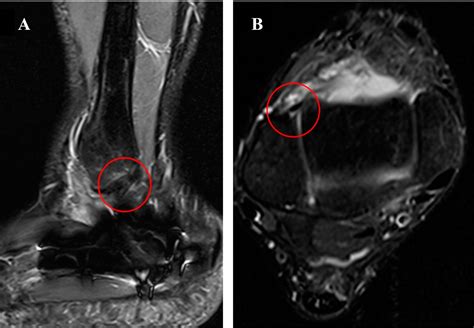

• MRI (Magnetic Resonance Imaging): The gold standard for visualizing soft tissue. An MRI can pinpoint the exact location and severity of the tear in the ligament.